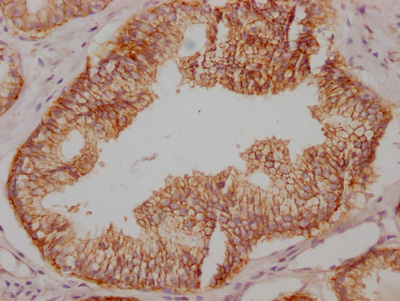

• IHC image of CSB-RA827145A0HU diluted at 1:100 and staining in paraffin-embedded human prostate cancer performed on a Leica BondTM system. After dewaxing and hydration, antigen retrieval was mediated by high pressure in a citrate buffer (pH 6.0). Section was blocked with 10% normal goat serum 30min at RT. Then primary antibody (1% BSA) was incubated at 4℃ overnight. The primary is detected by a Goat anti-rabbit IgG polymer labeled by HRP and visualized using 0.05% DAB.